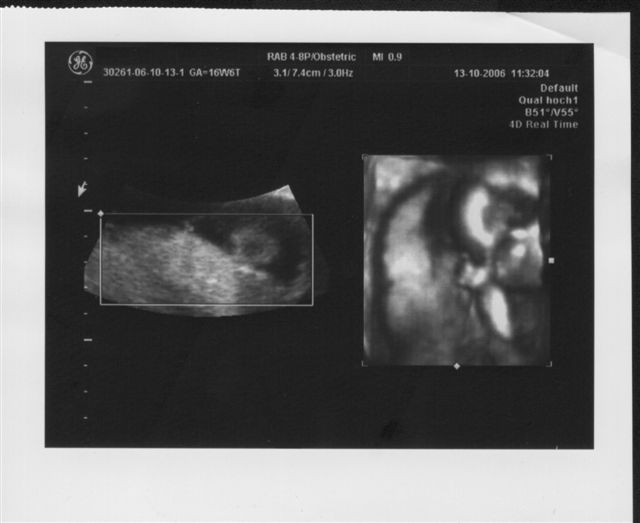

Ich war beim "Partner"-Doc der Gemeinschaftspraxis, in die mein Doc seit Juli eingestiegen ist. Dieser ist ebenfalls supernett und hat zudem noch ein 3D-Ultraschall, welches er mit auch gezeigt hat, nachdem er mit dem normalen Ultraschall alles "kontrolliert" hat. Es ist immer noch alles dran, ist alles zeitgerecht entwickelt. Nach der Gesamtgröße hab ich gar nicht gefragt, aber das Köpfchen hat 13 cm Umfang. Das ist genau Golfballgröße. Zum guten Schluss hat er mir dann noch ein 3D-Bild mitgegeben, auf dem man ohne Erklärung noch nicht wirklich viel erkennen kann. Das liegt u.a. auch daran, dass Krümel noch nicht genug Speck auf den Rippen hat und sich immer weggedreht ha - nicht ohne uns vorher zuzuwinken

Wieder war ich beim "Partner-Doc". Dieses Mal stand das 2. Screening an, das um die 20. Schwangerschaftswoche herum gemacht wird. Wahrscheinlich hätte "mein" Doc seinen Partner eh gebeten dies durchzuführen, weil er das modernste Gerät hat. Ich hab dann so nebenbei erfahren, dass er wohl der einzige Doc in Düsseldorf ist neben dem Praenatal-Zentrum und der Diakonie, der dieses Ultraschallgerät besitzt. Was ich bzw. wir bei diesem großen Ultraschall zu sehen bekommen haben, war umwerfend und zugleich auch ein bißchen erschreckend - erschreckend nicht, weil mit Krümel etwas nicht in Ordnung ist, sondern weil man so unglaublich viel sehen kann, also positiv erschreckend. Jedenfalls ist alles in bester Ordnung. Jedes Organ ist da wo es hingehört und funktioniert so wie es funktionieren sollte, nichts fehlt. Krümel ist zudem zeitgerecht entwickelt, sehr beweglich und aktiv. Außerdem lag Krümel so günstig, dass der Doc zwischendurch auf 3D bzw. 4D-Realtime umschalten konnte und wir so faszinierende Bilder gesehen haben. Die schönsten hat er mit ausgedruckt. Eines davon seht ihr oben. Und einen Fuß hat er noch "eingefangen". Der Kopfumfang ist seit dem letzten Mal um fast 3 cm gewachsen und Krümel ist insgesamt geschätzt 16 cm lang, wobei dies ein reiner Schätzwert ist und sowohl nach unten, eher aber nach oben abweichen kann. Ich bin sooo glücklich dass alles in Ordnung ist. Lars´ Augen haben beim Anblick der "Fotos" geleuchtet und meinte: "Mami, ich hab das Baby sooooo lieb!"

So und nu zeig ich noch das "Fuß-Foto" :